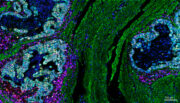

Speiseröhrenkrebs: Körpereigene Abwehr hilft bei der Therapie

Bei Patienten mit Speiseröhrenkrebs entscheidet nicht nur die Chemotherapie, sondern vor allem das Immunsystem über den Erfolg der Behandlung. Das zeigt eine jetzt veröffentlichte Studie unter maßgeblicher Beteiligung des Universitätsklinikums Freiburg.